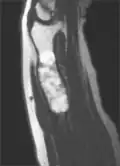

Magnetic resonance imaging (MRI), ultrasound, and scintigraphy are generally not practical for diagnostic purposes. X-rays are not as effective in the monitoring or evaluation of enchondromas due to frequent localized changes also sometimes due to the large number of enchondromas. MRI can sometimes however be used to monitor and evaluate symptomatic lesions in the case of potential malignant transformations.